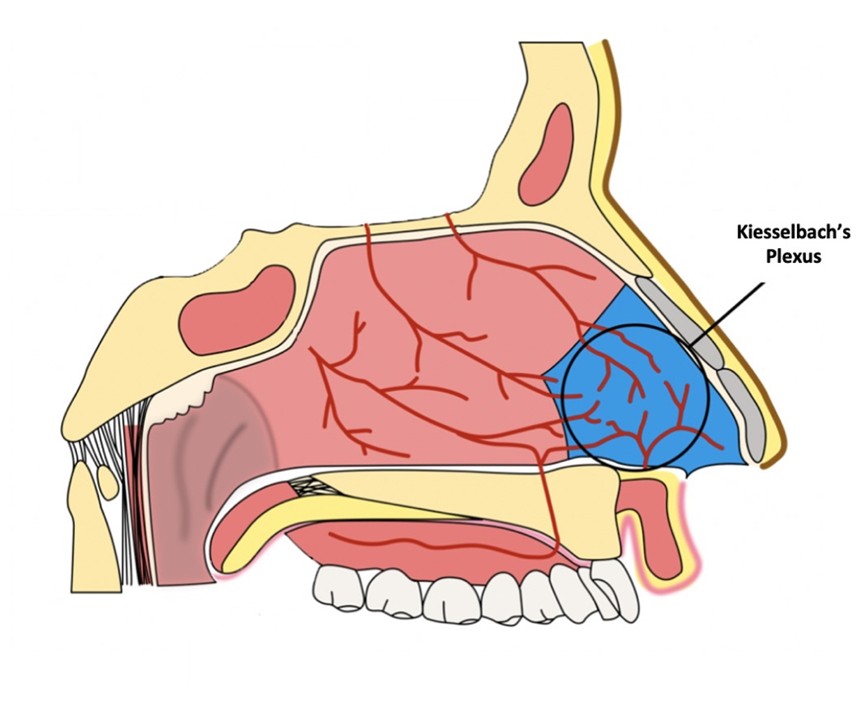

A cavidade nasal é uma região altamente vascularizada e na região mais anterior do septo nasal (mais próxima às aberturas das narinas) ocorre uma confluência de vasos, chamada área de Kisselbach. A anatomia dessa região, associada à sua localização mais próxima ao ambiente externo, fazem com que as epistaxes ali sejam mais frequentes.

Idosos possuem uma mucosa nasal mais frágil, sendo também frequentes epistaxes nessa região no caso de manipulação ou quando há uma baixa umidade com pouca hidratação nasal. O ressecamento do septo nasal pode lesar vasos sanguíneos da área de Kisselbach e como consequência sangramentos podem ocorrer.

A cauterização nasal em consultório normalmente é indicada em pacientes com sangramento da região mais anterior do nariz quando recente e sem controle ou quando este torna-se muito recorrente. Nesses casos é utilizada uma substância como o nitrato de prata ou o ácido tricloroacético embebida em algodão que realiza uma cauterização química no local do sangramento. Esse procedimento normalmente é necessário nos sangramentos recorrentes da área de Kisselbach.